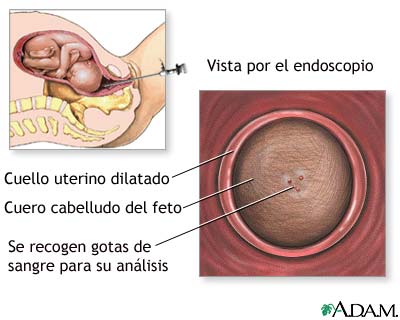

Examen fetal sale, Examen sanguineo fetal MedlinePlus enciclopedia medica illustracion sale

Examen sanguineo fetal MedlinePlus enciclopedia medica illustracion